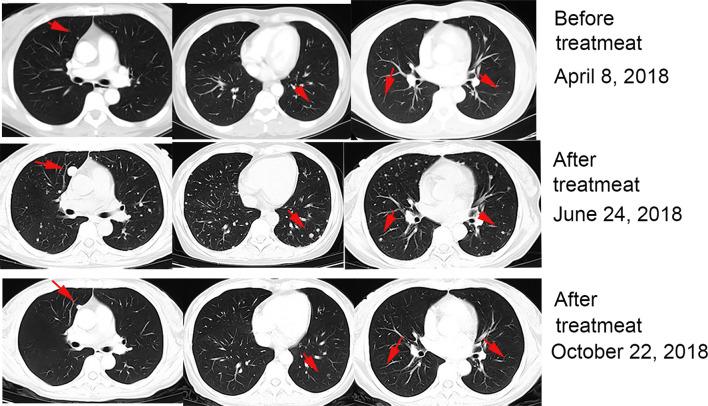

Treatment with a combination of programmed cell death-1 (PD-1) blocker and cytokine-induced killer (CIK) cells has improved outcome in cancer patients but is also associated with various patterns of responses. Pseudoprogression is a unique and uncommon phenomenon with no clear criteria for rapid diagnosis. Although some reports of pseudoprogression during immunotherapy exist, there are few reports of pseudoprogression occurring twice in the same patient. Here, we report the case of 51-year-old female patient with advanced renal cell carcinoma, who received a combination treatment of PD-1 blocker and CIK cells, and where pseudoprogression of lung and brain tumors occurred successively during treatment.

程序性细胞死亡蛋白1(PD-1)阻断剂与细胞因子诱导的杀伤细胞(CIK)联合治疗已改善了癌症患者的预后,但也与多种反应模式相关。假性进展是一种独特且罕见的现象,目前尚无快速诊断的明确标准。尽管已有一些关于免疫治疗期间假性进展的报道,但同一患者出现两次假性进展的报道却很少。在此,我们报告一例51岁晚期肾细胞癌女性患者,该患者接受了PD-1阻断剂与CIK细胞的联合治疗,治疗期间肺和脑肿瘤相继出现假性进展。